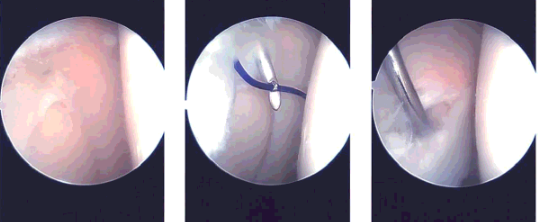

Arthroscopic set up was done and the time-out was called. A lateral entry portal was made and an arthroscope was inserted. The arthroscope was moved to the medial tibiofemoral compartment. A medial entry portal was made in a far medial position so as to reach the lateral meniscus easily. Shaver was introduced.

Examination of the medial compartment showed intact meniscus as well as chondral surfaces. Debridement of the intercondylar notch was done to remove the ligamentum patellae. The ACL was intact.

Examination of the lateral tibiofemoral compartment showed tear in the anterior horn as well as partial tear in the anterior root. The tear in the anterior horn was in the red-white zone and it was decided to repair it. Debridement of the anterior root of the lateral meniscus was performed.

The tear was prepped with the use of meniscal rasp and shaver. Outside-in repair was planned. Meniscal mender was opened and the straight needle was passed percutaneously laterally through the meniscus tear. The probe needle was advanced at the side of the straight needle through the tear.

Once it was in, the snare was passed out of the probe needle and PDS suture was passed through the straight needle The PDS suture was retrieved. A skin incision was given connecting the two sutures.

The PDS suture was replaced by #2-0 FiberWire. The repair was checked arthroscopically and found to be in a satisfactory position. The suture was knotted on the outside.

Examination of the rest of the lateral tibiofibular femoral compartment showed intact meniscus in the posterior horn as well as intact bone and cartilages. Examination of the patellofemoral compartment showed intact cartilage and no maltracking.

The final picture was taken and saved. The knee was thoroughly irrigated. To perform microfracture chondroplasty in the intercondylar notch to release the marrow into the knee to allow a good healing environment. Knee was drained completely.

Intraoperative images